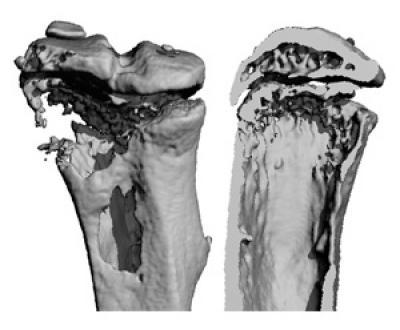

Investigational cancer drugs, IAP antagonists, may increase the risk of tumors spreading to bone. Tumors often cause bone loss, but IAP antagonist treatment accelerates the problem. The images show a bone with a tumor from a mouse treated with IAP antagonist BV6. The bone destruction is substantial, with gaping holes (left) and near total loss of the interior spongy bone (right).

(Photo Credit: Chang Yang, M.D., Ph.D.)